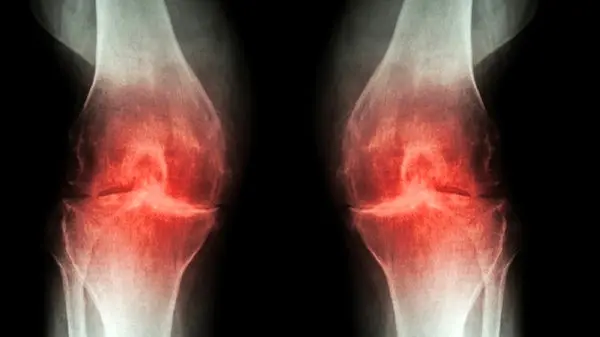

درمان دردهای مفصلی در طب سنتی

دردهای مفصلی بسیاری از افراد را درگیر کرده است. دردهای مفصلی موجب خستگی زودرس در طول روز می شود. مهم ترین عامل در دردهای مفصلی تحرک نداشتن و ثابت برای مدت طولانی در یک جا نشستن است. درمان دردهای مفصلی را باید جدی گرفت تا کهنه نشود و مشکلات حاد برای فرد ایجاد نکند. طب سنتی راهکارهایی را برای درمان دردهای مفصلی ارائه داده است.

علیرضا یارقلی متخصص طب سنتی درباره این موضوع که علائم بیماری‌های مفصلی در تابستان با باد کولر و پنکه افزایش می‌یابد، گفت: زندگی ماشینی باعث شده اتاق‌های ما در تابستان سردتر از زمستان باشد. زندگی ماشینی و بدن‌های پُر و بد انباشته باعث شده تا در تابستان زیر کولر و پنکه باشیم و طاقت گرما نداشته باشیم و این امر موجب سردی اولیه مزاج بدن می‌شود و شاهد درد و کوفتگی مفاصل هستیم در فاز‌های بعدی دچار ریزش ماده و ورم مفاصل هم می‌شویم که خطرناک‌تر است.

این متخصص طب سنتی ادامه داد: در یک خانه افرادی با مزاج‌های مختلف زندگی می‌کنند هرچه سن بالا می‌رود مزاج به سمت سردشدن می‌رود. افراد زیر ۲۵ سال مزاج گرم و‌ تر دارند و تا ۴۰ سال گرم و خشک و تا ۶۰ سالگی مزاج، سرد وخشک می‌شود. بعد از این سن رطوبتی به بدن اضافه می‌شود که موجب دست و پا درد افراد مسن می‌گردد و با سرما فرآیند‌های التهابی روماتیسم و دردی مفاصل به آن اضافه می‌شود و به دلیل اضافه وزن و کاهش متابولیسم چرخه‌ای از بیماری‌ها به وجود می‌آید.